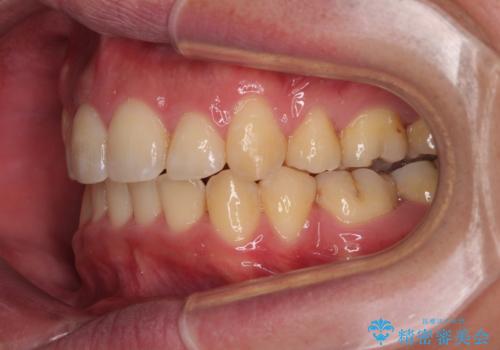

- デコボコと前歯の突出感を気にして来院された患者様です。

舌の突出癖などにより上顎前歯が前方に突出し、さらに歯列幅が狭小になっている状態でした。

また、上顎歯列全体が下顎に対して前方位に位置していました。